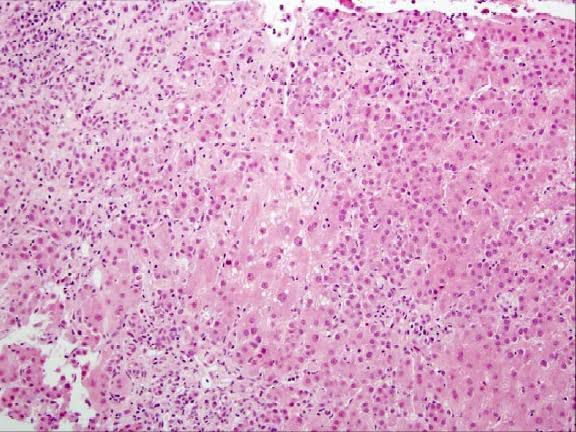

Acute Hepatitis

Acute hepatitis is a term used to describe a wide variety of conditions characterized by acute inflammation of the hepatic parenchyma or injury to hepatocytes resulting in elevated liver function indices.